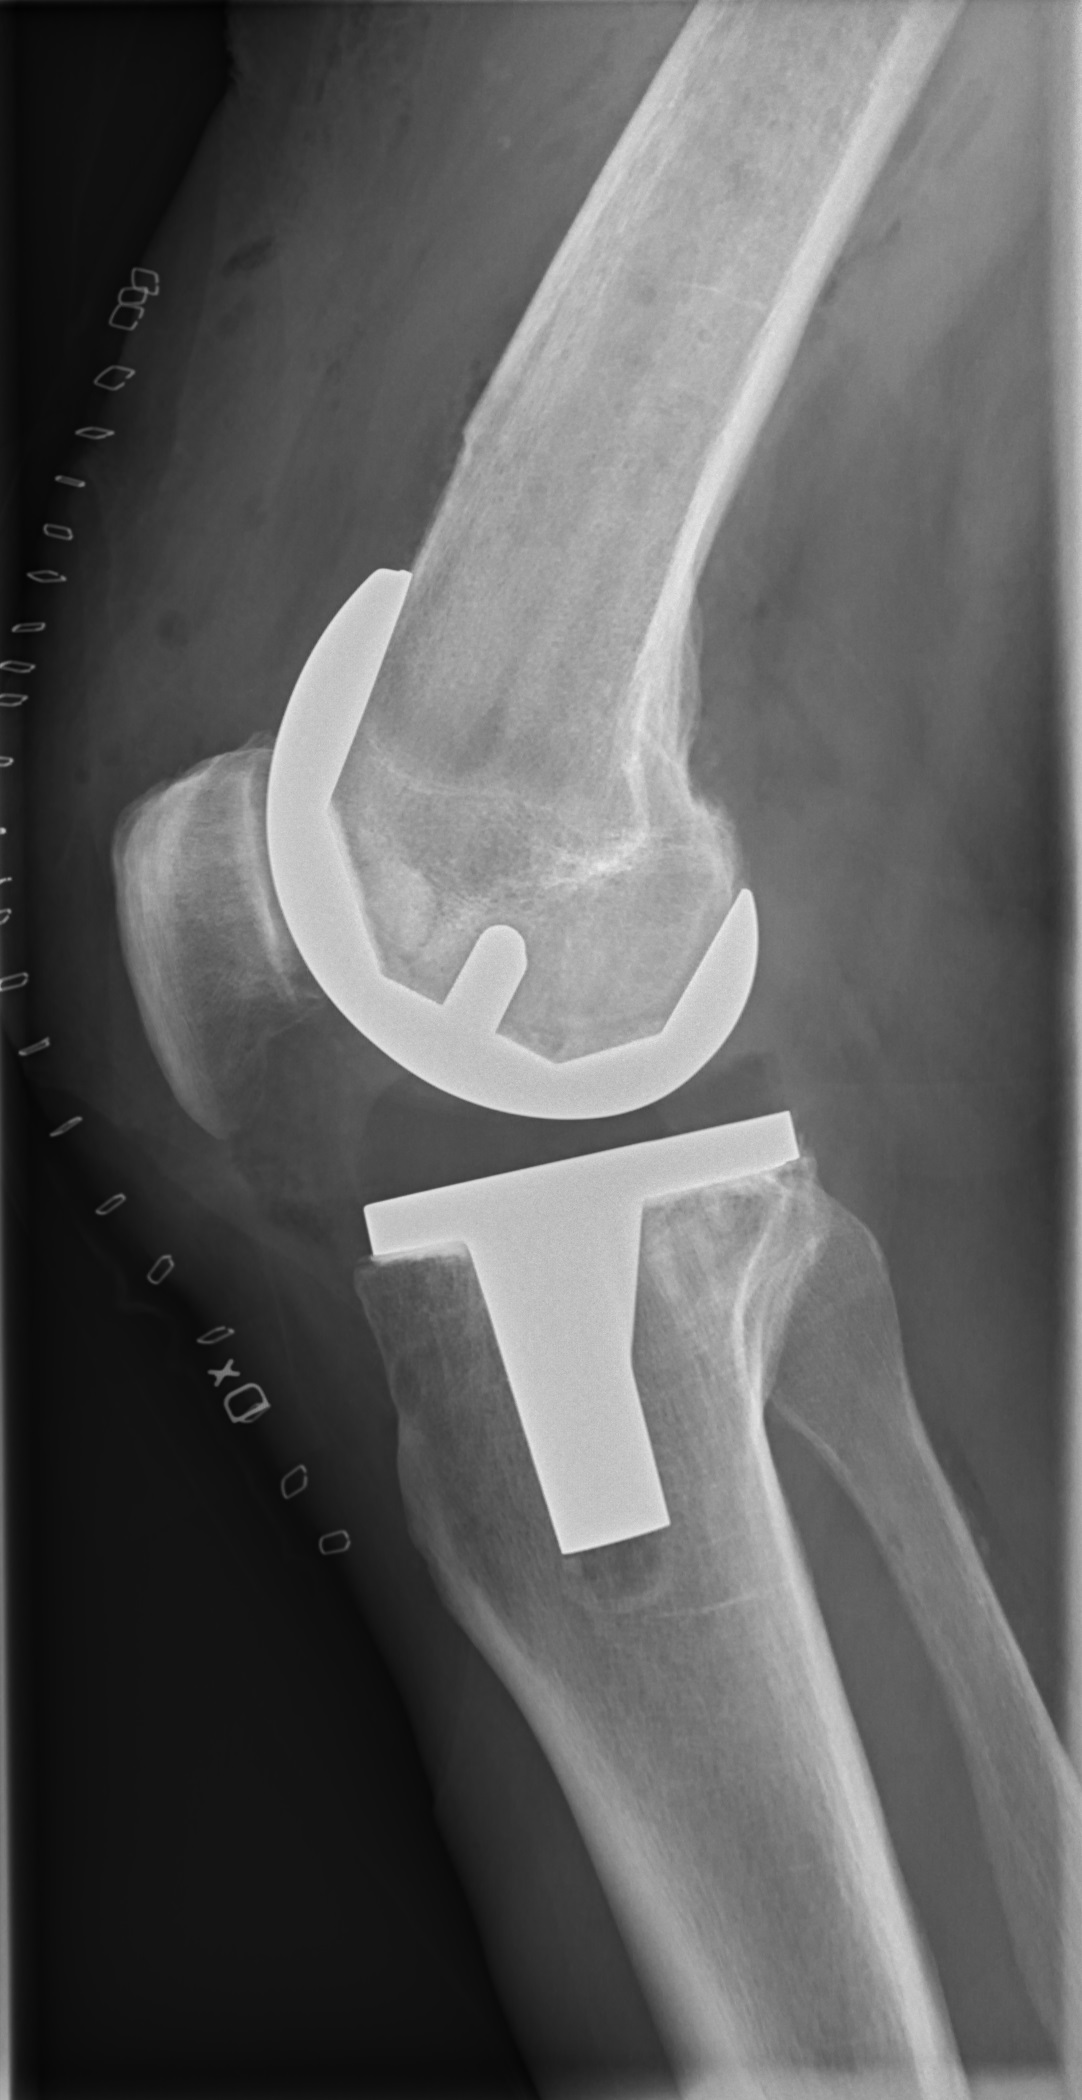

Die Verletzung ereignete sich in einem Vorbereitungsspiel, woraufhin Matriciani frühzeitig ausgewechselt werden musste. Spätere Untersuchungen bestätigten einen Riss des vorderen Kreuzbands im linken Knie. Noch in dieser Woche soll er operiert werden – für den Rest der Saison fällt er damit aus.